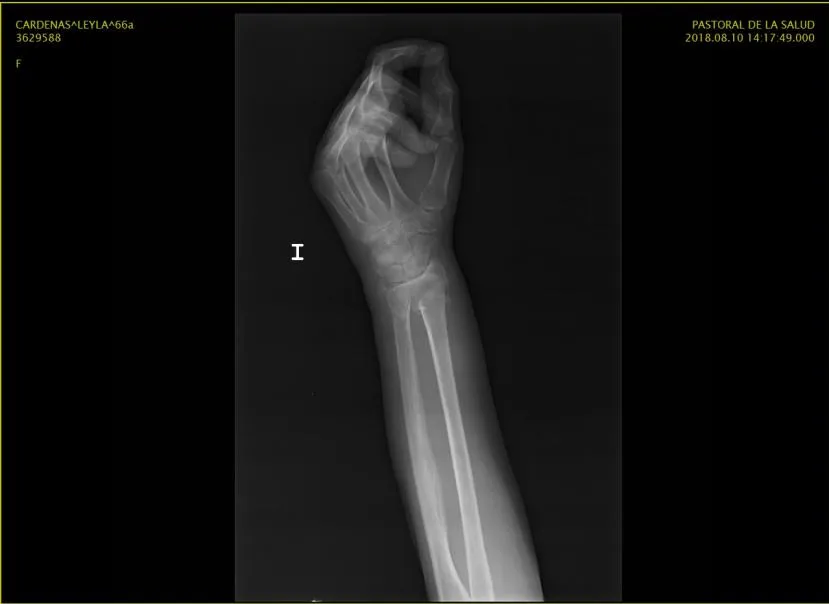

El día Viernes 10 de Agosto del presente año una gran amiga de la familia, madrina de dos de mis hijos, sufrió una fuerte caída afectando su mano Izquierda presentado Fractura de 1/3 distal del radio con desplazamiento del fragmento distal en sentido posterior y radial.

Mando a solicitar las imágenes de RX para ver que estaba sucediendo el día Domingo. mi querida amiga vive en otra ciudad no muy lejos de la mía pero aun así pues estaba un tanto lejos, así que mi papá le toco viajar para buscar las imágenes y cuando las reviso me pareció raro el diagnostico del medico, no porque no fuera grave sino porque estaba solicitando una cirugía que a mi parecer no iba al caso. Para muchos es conocido que trabaje por varios años en el área de salud como analista de seguros en el área de clave de emergencia, ademas de ser supervisora de admisión en una clínica, me toco revisar muchos casos para no decir cientos de ellos, donde evalué diagnósticos similares y me tocaba decidir si procedía el ingreso o no a cirugía.

Estas son las imágenes de Rx de mi amiga

A mi parecer este tipo de traumatismo solo llevan una maniobra que lleva el hueso a su lugar y se le coloca un yeso para mantener protegida la zona mientras se hace el proceso de sanación de la zona afectada, pero como no soy traumatologa no puedo afirmar o desmentir a un especialista. Acto seguido llamo a la clínica de traumatología en donde trabaje como supervisora de admisión, en la cual siempre me han atendido con un amor incondicional debido a todo los buenos momentos que allí pase, converso con mi antigua jefa (cabe destacar que es una excelente persona con un carisma impresionante) y le pido ayuda para que un medico de la clínica atendiera el caso y me diera su evaluación.